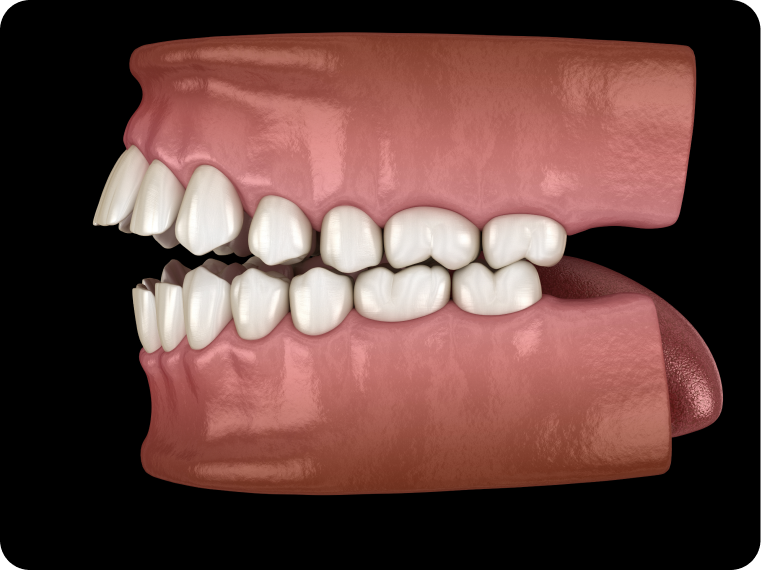

La béance incisive, par exemple, correspond à l’absence de contact entre les incisives du haut et celles du bas lorsque la bouche est fermée. Une morsure palatine, quant à elle, se caractérise par un recouvrement excessif des incisives supérieures sur les incisives inférieures, parfois jusqu’à toucher le palais.